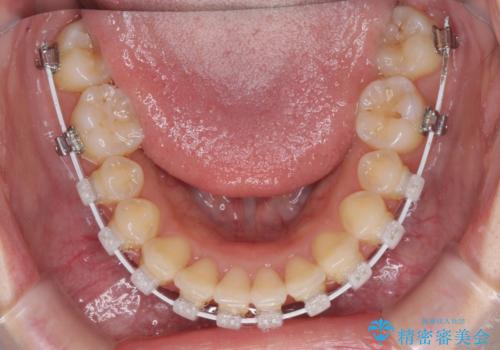

- 矯正装置

- 審美装置

より治療を速やかに行うため、上顎右側にアンカースクリューを使用し、目標としていた1年半ほどで治療を終えることができました。